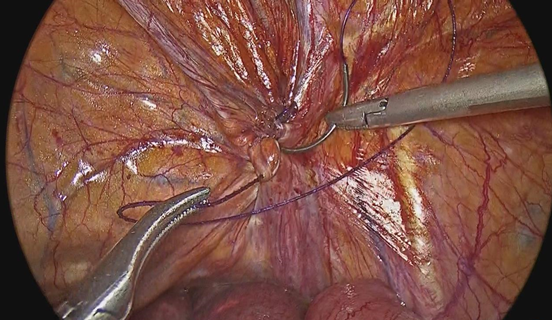

A 93-year-old woman presented to the emergency department with a 1-day history of right lower quadrant abdominal pain that moved into the right groin area. On physical examination, presented with left lower quadrant pain, decreased peristaltic sounds and abdominal distension. Laboratory data demonstrated leukocytosis. Abdominal computed tomography showed an incarcerated right femoral hernia of the appendix with dilatation of the appendix (Figure 1 & 2). She underwent laparoscopic surgery where an incarcerated colon was observed in the internal ring of the right femoral canal (Figure 3 & 4). Appendectomy was performed after reduction (Figure 5). The right femoral hernia of the internal ring was closed with a primary suture (Figure 6 & 7). Pathologic anatomy revealed appendicitis with reactive lymphoid aggregates. From the beginning he was treated with antibiotics, and adequate parenteral fluid management. The postoperative period was adequate, she did not present abdominal symptoms such as pain or nausea. She was discharged 4 days after a successful appendectomy and hernia repair.

Figure 5 Appendectomy with endoloop is performed without complications.

Figure 6 Primary closure of the hernia defect with barbed suture was performed without complications.